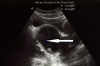

Figure 2

Right pyocolpos: Longitudinal transabdominal sonographic image through the pelvis demonstrates cystic structure with echogenic material inside, representing distended right upper hemivagina.